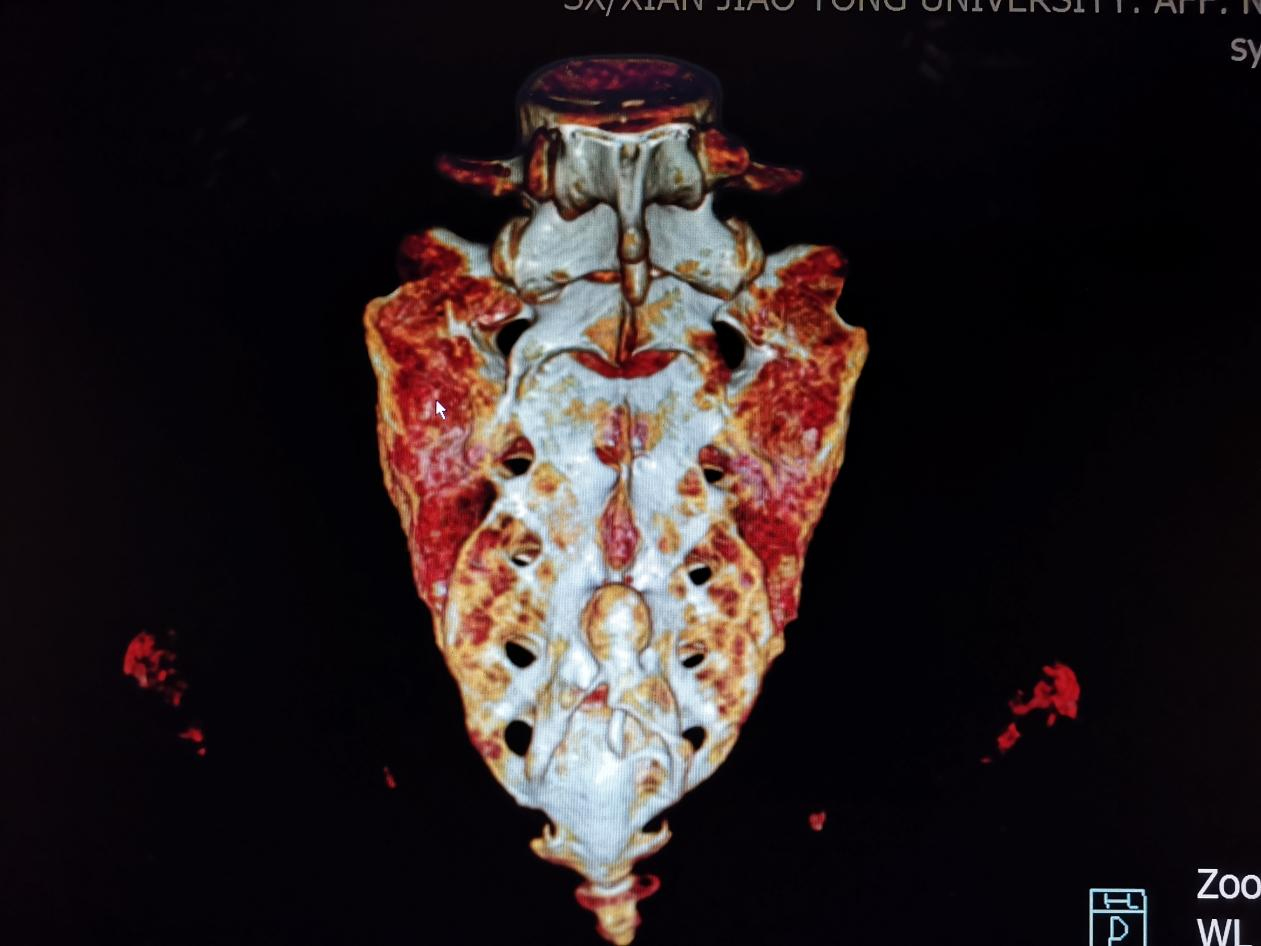

患者入院后,医护小组引导患者完善相关检查,综合评估病情,考虑诊断为复杂的腰骶神经损伤导致排尿排便功能障碍;CT提示患者系变异骶骨、五对骶孔等多发畸形(如下图所示),种铁教授带领科室医护团队认真讨论病情,分析骶神经调控疗法对患者可能是一种有效的治疗方案,经与患者充分沟通,为患者实施了一期体验电极植入手术。

(骶骨三维重建)